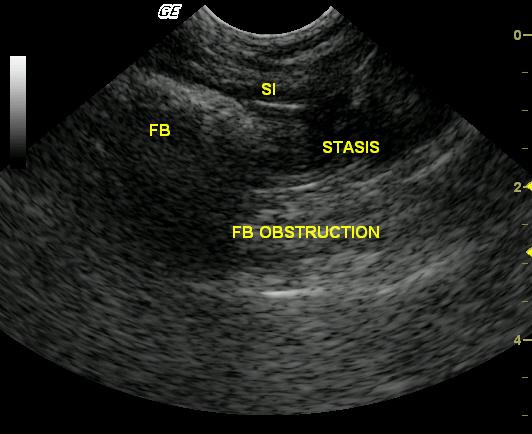

This 12-year-old FS DSH cat was presented with a short history of eating plants, vomiting hairballs, and anorexia that was non-responsive to hospitalization and intravenous medical treatment. Clinical exam revealed a doughy abdomen, and mild hypothermia. Blood analysis revealed mild neutropenia and hypoalbuminemia.